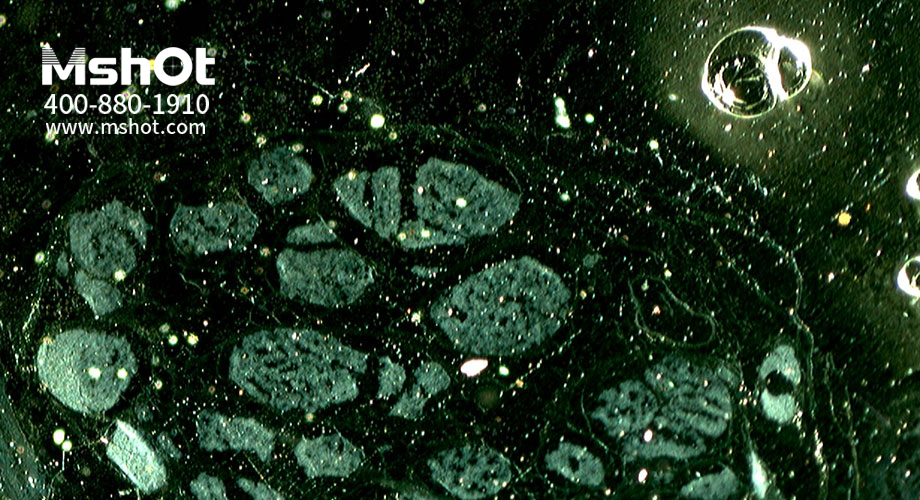

神經(jīng)纖維切片顯微圖片。 (操作提示:點擊圖片或使用鍵盤上的方向鍵來轉(zhuǎn)換要查看的圖片)